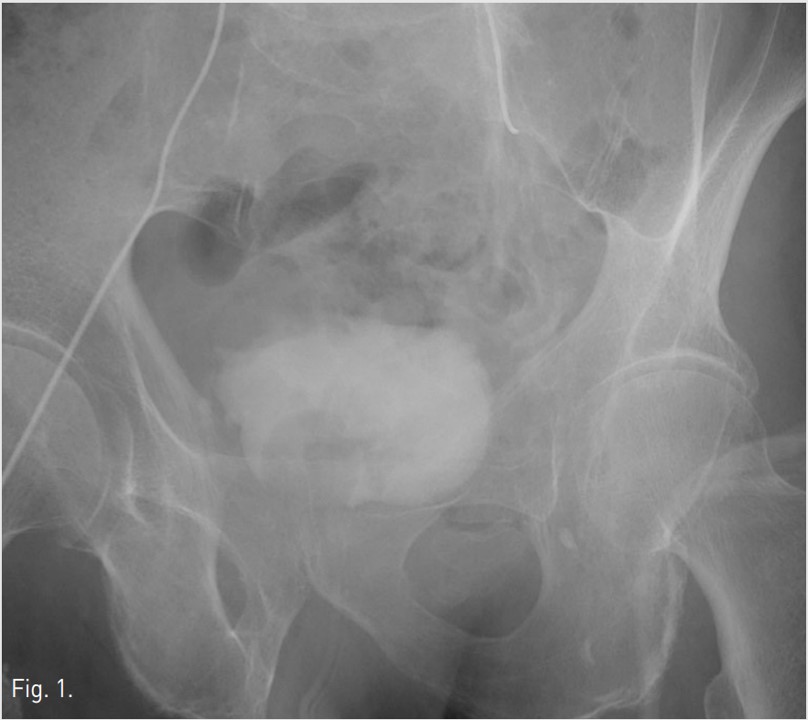

Fig. 2.

Fig. 2. Selective left internal iliac angiogram shows some prominence of the left vesical artery(arrows) running around the distended urinary bladder.

방광을 희석된 조영제로 채운 후 얻은 좌측 내장골동맥조영 사진에서 좌측 아래방광동맥(inferior vesical artery)이 두드러지게 커져 보임(Fig. 1, 2). 우측 내장골동맥조영 사진에서는 이상소견 보이지 않음.

우측 총대퇴동맥을 역방향천자하여 5F sheath(Terumo, Tokyo, Japan)를 삽입함. 5F Robert uterine catheter(Cook, Bloomington, USA)를 사용하여 좌측 내장골동맥을 선택한 후 방광에 삽입되어 있는 Foley catheter를 통해 10%로 희석된 조영제 100ml를 방광 내로 주입한 다음 동맥조영술을 시행함(Fig. 1, 2). 좌측 내장골동맥조영술에서 좌측 아래방광동맥이 두드러지게 커져 보여, 좌측 방광동맥을 미세도관(Progreat, Terumo, Tokyo, Japan)과 미세유도철사(GT wire, Terumo, Tokyo, Japan)로 superselection한 다음 gelfoam으로 색전하였음(Fig. 3). 색전술 시행 후 얻은 좌측 내장골동맥조영술에서 더 이상 방광동맥이 보이지 않았음(Fig. 4) 우측 내장골동맥조영술에서는 이상소견 보이지 않아 우측에서는 색전술을 시행하지 않음. 이후 환자는 혈뇨 증상이 호전됨.